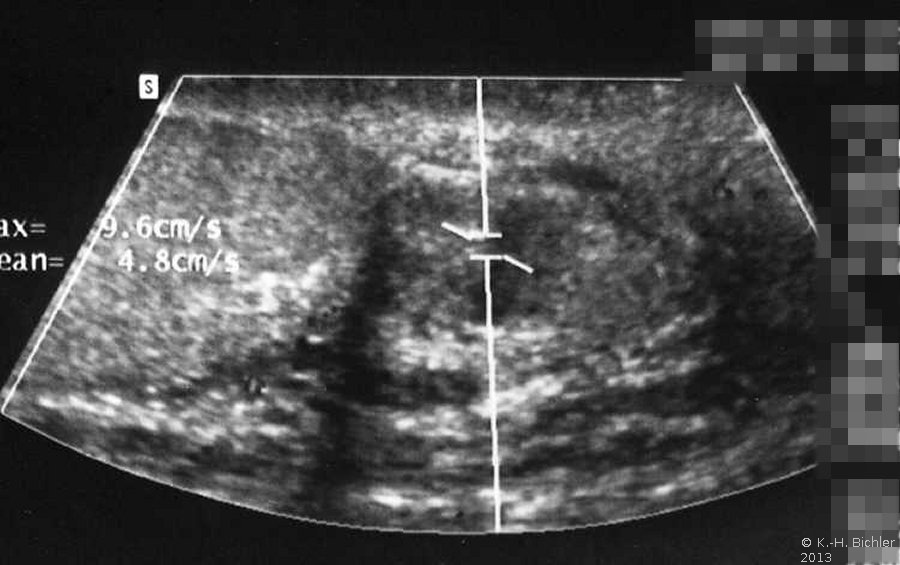

Sonographie: Vergrößerter und destruierter Nebenhoden (Abbildung 2).